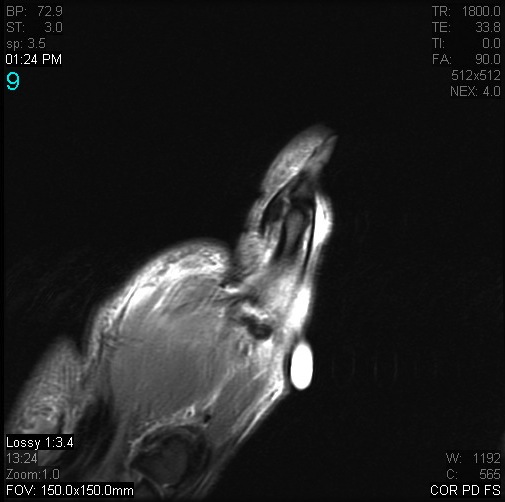

Figure 2 for case Stener lesion

Figure 2